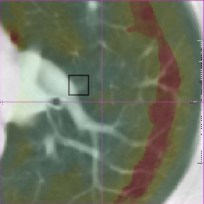

with 𝒙Fsubscript𝒙𝐹\bm{x}_{F} and 𝒙Msubscript𝒙𝑀\bm{x}_{M} the corresponding landmark locations. Based on the idea that the registration error is smooth, we include voxels from a small local neighborhood around the landmarks to increase the total set of available landmarks. In this small neighborhood we assume that the registration error is equal to the error at the center of the neighborhood. This assumption seems reasonable for smooth transformations and within a small region. The neighborhood size is chosen as 10×10×7.5mm10107.5mm10\times 10\times 7.5\;\mathrm{mm}, which is approximately equivalent to the final grid spacing of the B-spline registration (see Fig. 5).

Refer to caption

() Ground truth

(a) Predicted error

(b) Magnification of (a)

(c) Magnification of (b)

Figure 5: Example data from the SPREAD dataset. The left column (a,c) shows the fixed image with the ground truth registration error overlaid in color. The square boxes around each landmark are given the same error as the error at the landmark. The right column (b,d) shows the moving image after registration with the registration error predicted by the proposed method overlaid in color. (c) and (d) are zoomed in versions of (a) and (b).